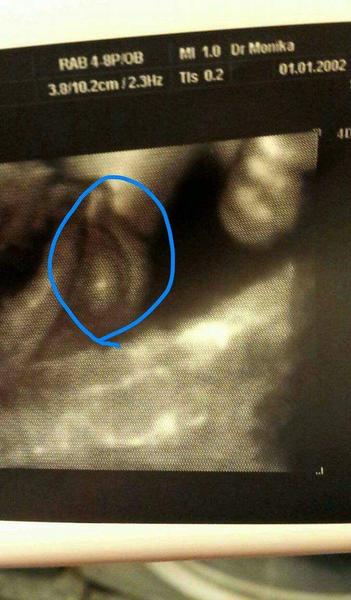

Je to 37tt a prave ze jeden doktor povedal dievca a falsi chlapcek ... nevedia ci je to pindik ci klitoris ....

@davlinka pokud si nejsou jisty zda je to pindour nebo klitoris. Tak by se mel dr.podivat zda to co vypadá jako buchticka. Tak jestli to neni pytlik a v nem sestoupli jiz v tomto tydnu varlatka. Me takhle muj dr.identifikoval druhe syna a ted ve 32tt mi tez ukazoval pouze pytlik a ze v nem ma uz sestouple jedno varlatko.

Uvidime ked sa narodi tam to uz bude nezvratne ci chlapcek ci dievcatko mna furt metie to ze tam ma ako by pindika ale zase spodok nevyzera ako vajicka ale ako pindulka jak to kavove zrno

mariejosef ptam da aj pre to ze chlapca uz mam ....a naozaj to takto nevyzeralo ale furt ma pletie to stojace hore ci to neni nahodou fakt pipik a vajicka

@davlinka na te druhe fotce se neorientuju,ta prvni je matouci,opravdu to muze byt oboji,i kdyz mne to prijde vic jako kavove zrno,mi prijde,ze tam je videt ten pysk uprostred. Tak jsem zvedava. Skoda,ze nemas jinou fotku. Co z 20tt?